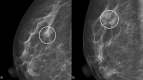

Radial scar (RS) or complex sclerosing lesions (CSL) if > 10 mm is a benign lesion with an increasing incidence of diagnosis (ranging from 0.6 to 3.7%) and represents a challenge both for radiologists and for pathologists. The digital mammography and digital breast tomosynthesis appearances of RS are well documented, according to the literature. On ultrasound, variable aspects can be detected. Magnetic resonance imaging contribution to differential diagnosis with carcinoma is growing. As for the management, a vacuum-assisted biopsy (VAB) with large core is recommended after a percutaneous diagnosis of RS due to potential sampling error. According to the recent International Consensus Conference, a RS/CSL lesion, which is visible on imaging, should undergo therapeutic excision with VAB. Thereafter, surveillance is justified. The aim of this review is to provide a practical guide for the recognition of RS on imaging, illustrating radiological findings according to the most recent literature, and to delineate the management strategies that follow.